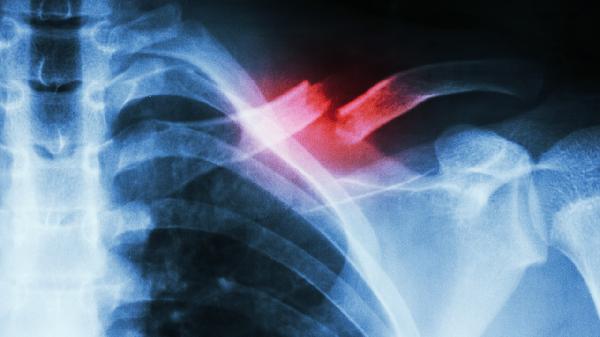

病理性骨折通常表现为局部疼痛、肿胀、活动受限,可能由骨质疏松、骨肿瘤、骨髓炎、骨代谢异常、长期激素治疗等因素引起。

原发性骨肿瘤如骨肉瘤或转移性骨肿瘤均可破坏骨质结构。患者可能出现持续性骨痛、夜间痛加重、局部肿块等症状。肿瘤导致的骨折常见于承重骨如股骨、椎体。治疗需根据肿瘤性质选择手术切除、放疗或化疗。恶性肿瘤导致的骨折预后较差,需密切随访。